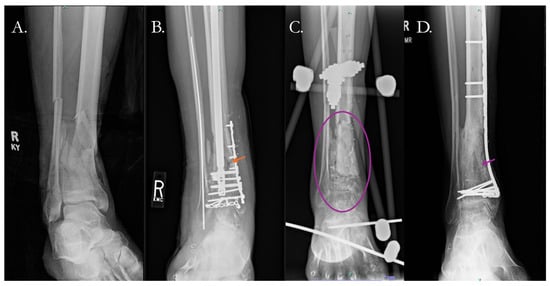

4.2.1. Traditional Surgical Approaches

4.2.2. Surgical Solutions with Biologic Therapy